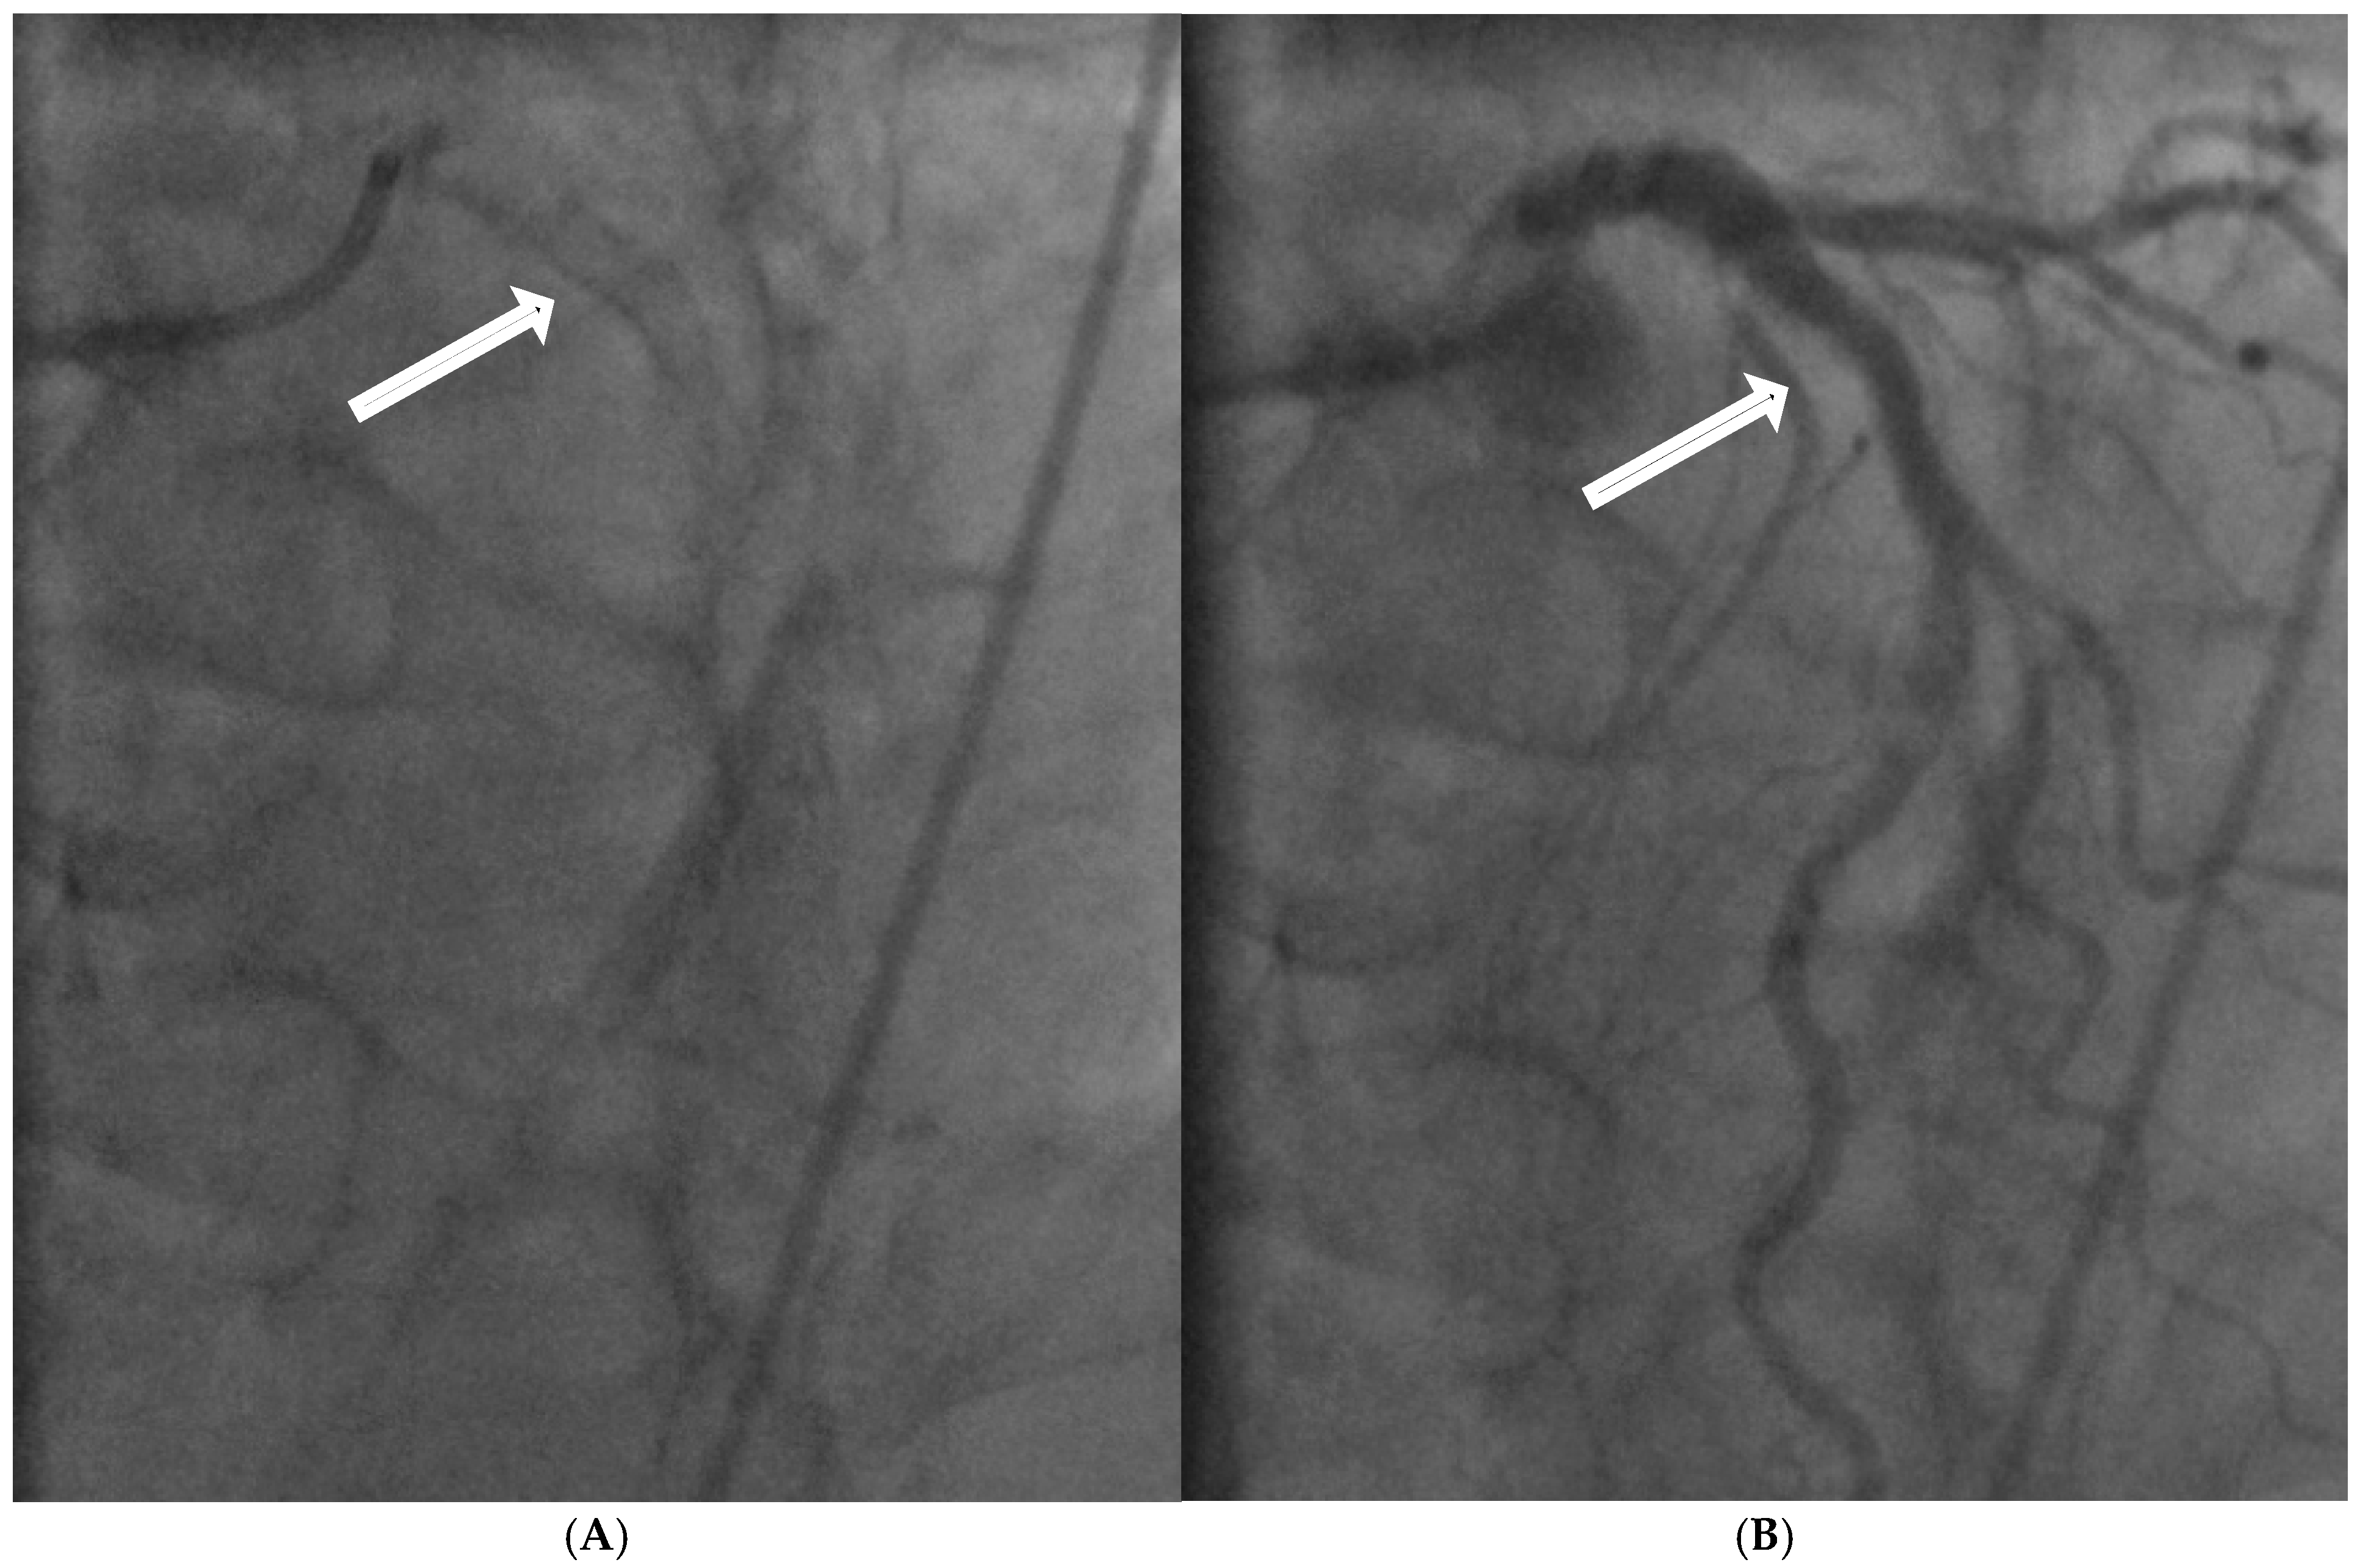

2.3. Local Intimal Ischemia Due to Thick Boundary Layer

- Fluid Mechanics Perspective:

- Coronary Angiographic Perspective: